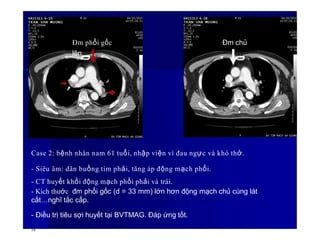

Case 2: bệnh nhân nam 61 tuổi, nhập viện vì đau ngực và khó thở.

- Siêu âm: dãn buồng tim phải, tăng áp động mạch phổi.

- CT huyết khối động mạch phổi phải và trái.

- Kích thước đm phổi gốc (d = 33 mm) lớn hơn động mạch chủ cùng lát

cắt…nghĩ tắc cấp.

- Điều trị tiêu sợi huyết tại BVTMAG. Đáp ứng tốt.